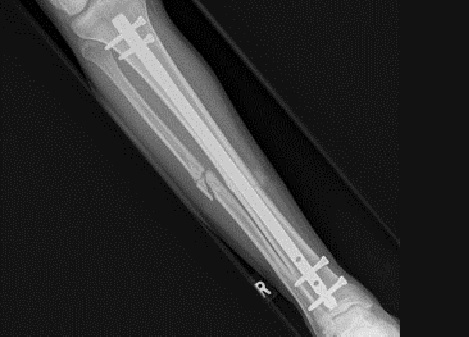

Fig6. - Midshaft tibia fracture.

Fig6. - Treated with an intramedullary nail